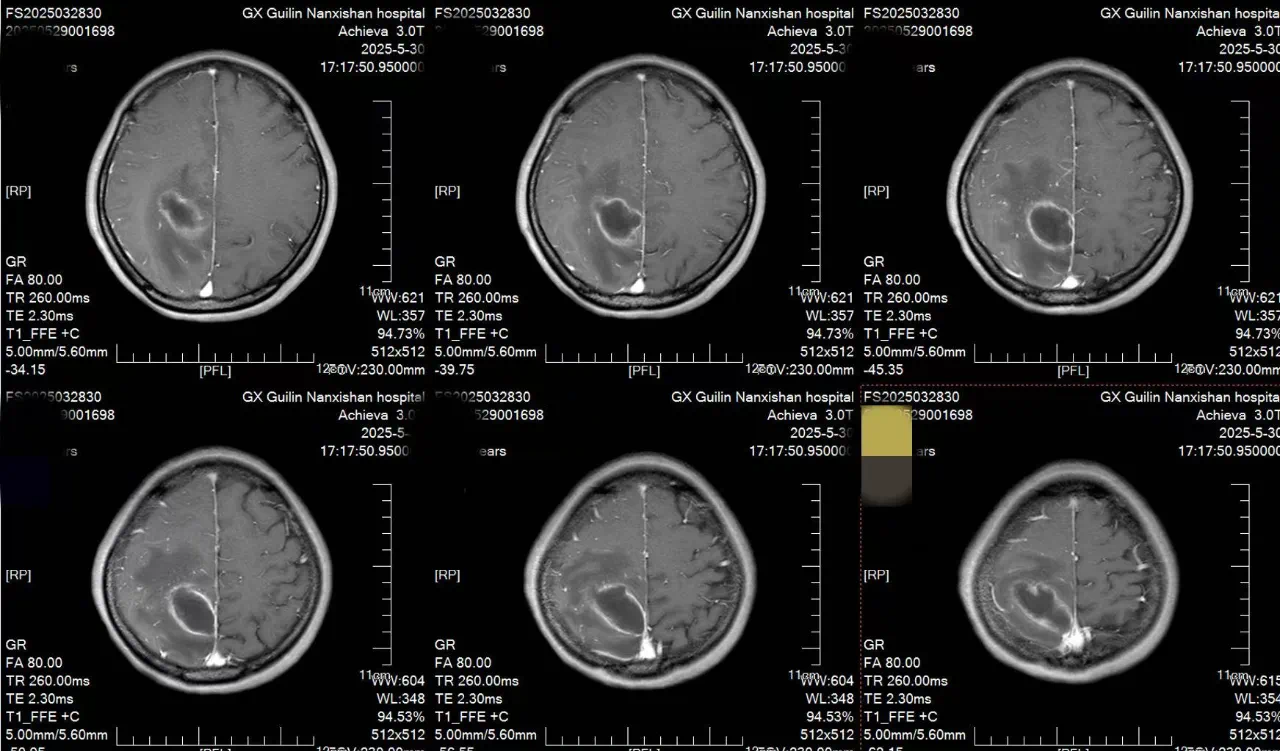

面对李女士的病情,神经外科团队经过反复讨论,决定采用机器人辅助实时可视化抽吸微创手术。手术前,团队通过3D影像重建技术,为李女士的脑部构建了精准的三维模型,清晰标注出脓肿的大小、形态以及与周围血管、神经的位置关系。手术机器人则根据这些数据,自动规划出最优穿刺路径,误差可控制在0.5毫米以内。

在机器人“导航”系统的引导下,神经外科主任王文波主任医师手持穿刺针,沿着预设路径稳步推进。术中,实时影像系统如同“透视眼”,清晰显示穿刺针的位置和脓肿内部情况,医生可以动态观察抽吸过程,确保每一步操作都精准无误。传统开颅手术需要打开十几厘米的切口,创伤大、恢复慢,还可能引发感染。而机器人辅助手术不仅创伤小,还能最大限度减少对正常脑组织的干扰。术后李女士肢体功能逐渐恢复,一周后完全恢复。